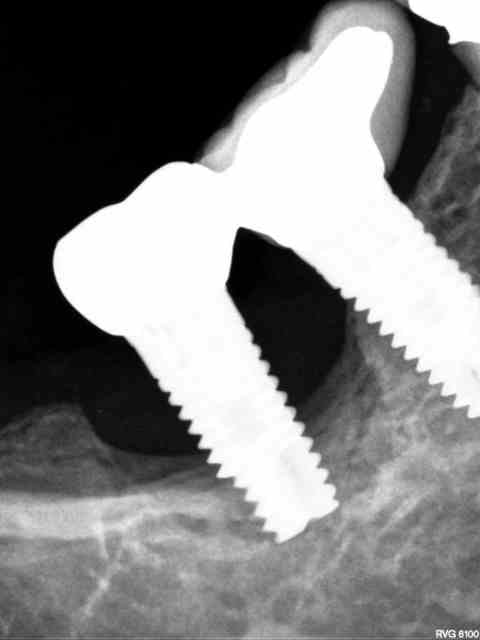

le "truc" que je comprends pas: pourquoi juste la 35, sachant que l'occlusion et la fonction sont OK, pas de problème d'adaptation de la prothèse, ni de présence de ciment...

j'en suis à me demander si c'est pas un abcès "paro" (je devrais dire périimplantaire) suite à une blessure avec un aliment (genre crustacés stars des fêtes de fin d'année)...

Comme ça , à brûle pourpoints je dirais que les appuis étant plus important à gauche qu'à droite + l'effet piston de 23 et 25 (sur 35) + l'environnement osseux de cette zone (de part et d'autre du trou mentonnier)... mais bon je ne suis pas implanto , ce n'est qu'un simple avis mécanique . Je me demande si l'occlusion générale n'y est pas pour qq chose .

Plan B: les points de contacts interproximaux sur 35 , forcés par l'effet piston de 23 et 25 .

points de contacts ok, vérifiés, zéro mobilité, occlusion ok, mouvements propulsion/latéralités ok...

ce que je ne comprends pas c'est pourquoi je n'ai pas de perte en lingual (c'est vrai que c'est pas facile à voir sur nonol, mais il n'y a pas de perte osseuse en lingual...çà forme une cuvette en forme de "croissant" avec point bas vestibulaire) ou du moins pas encore...